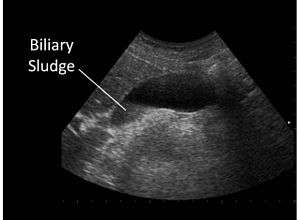

Biliary sludge in gallbladder on ultrasound

Biliary sludge is typically diagnosed by CT scan, transabdominal ultrasonography.[1][2] Endoscopic ultrasonography is another more sensitive option. However, the gold standard is considered to be direct microscopy of aspirated gallbladder bile.[1][2] This method is much more sensitive, although it is less practical.[2]